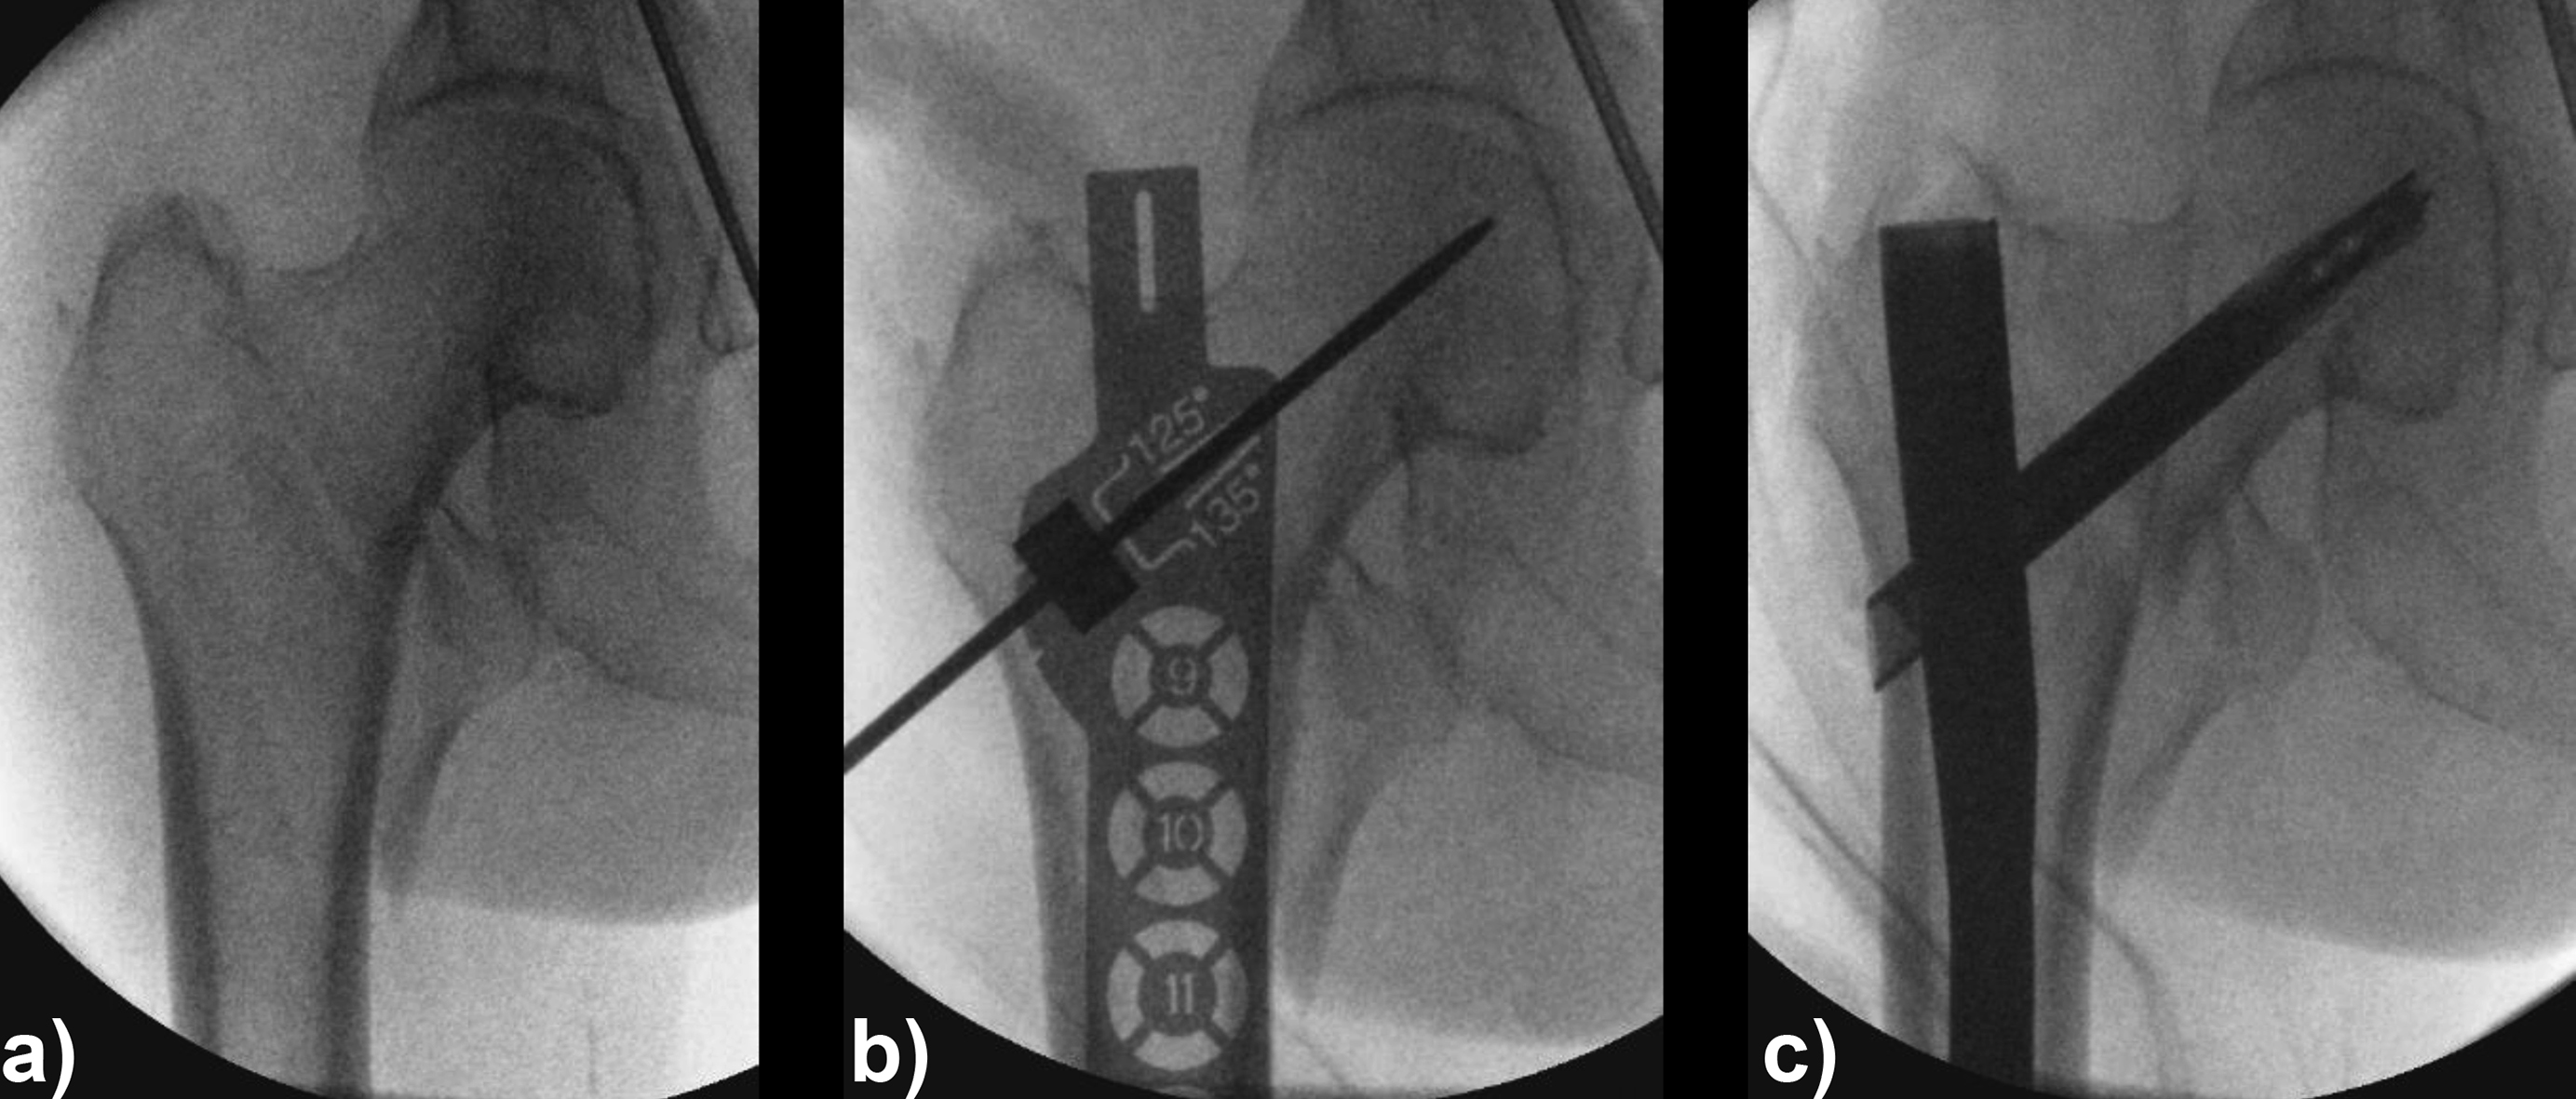

An 83-year-old female patient sustained a 31-A.2.2 fracture of the right proximal femur after a fall at home (Figs 1-2). Intraoperative and postoperative images are shown (Figs 3-5).